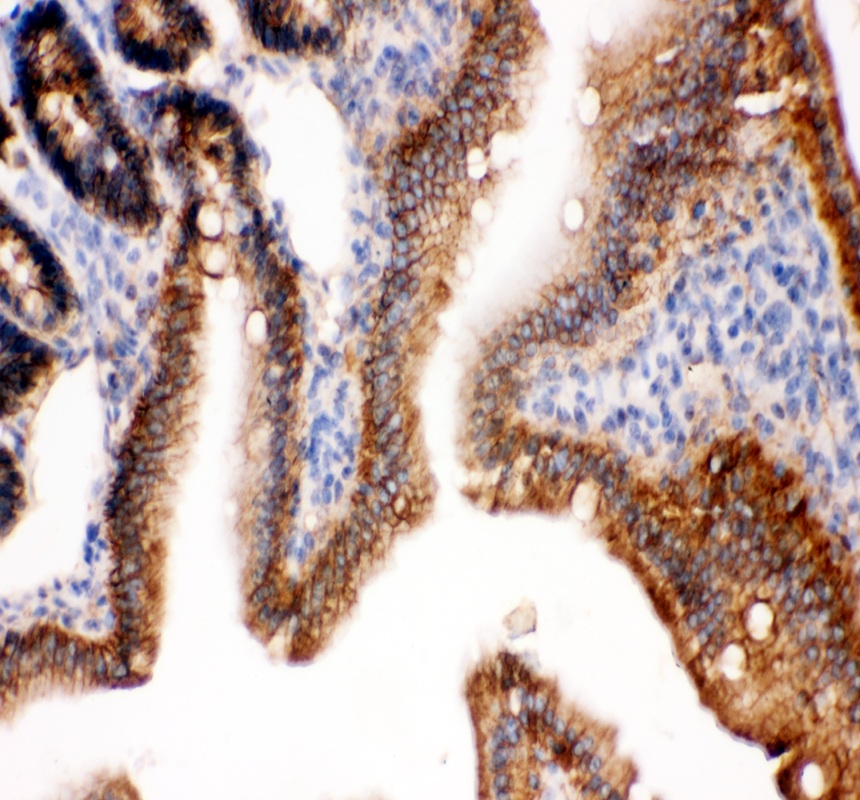

IHC analysis of E-cadherin/CDH1 using anti-E-cadherin/CDH1 antibody (PB9561).

E-cadherin/CDH1 was detected in a paraffin-embedded section of mouse colon tissue. The tissue section was incubated with rabbit anti-E-cadherin/CDH1 Antibody (PB9561) at a dilution of 1:200 and developed using HRP Conjugated Rabbit IgG Super Vision Assay Kit (Catalog # SV0002) with DAB (Catalog # AR1027) as the chromogen.